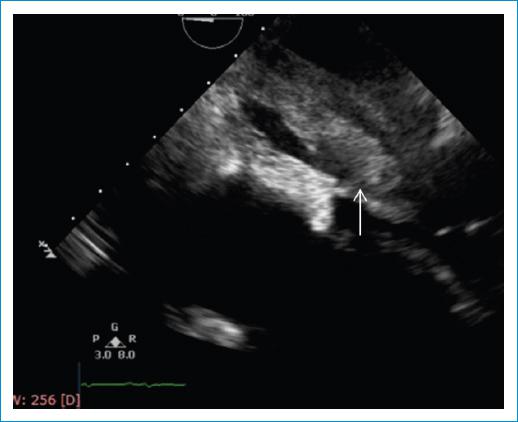

El electrocardiograma documentó único hallazgo de taquicardia sinusal. Entre los paraclínicos de ingreso se encontró INR en rangos terapéuticos (2.7) hipoalbuminemia, gases arteriales con evidencia de acidosis metabólica con anión Gap normal con hipoxemia moderada (Tabla 1) y radiografía de tórax simple con evidencia de edema pulmonar en fase intersticial (Fig. 1).Se complementó con ecocardiograma transtorácico, el cual reportó una masa en la aurícula izquierda, que parecía estar adherida a su pared posterior y obstruía el tracto de entrada del ventrículo izquierdo (Fig. 2). Fue valorada por el equipo de cirugía cardiovascular quienes indicaron la toma de ecocardiograma transesofágico, el cual permitió una mejor caracterización de la lesión; en este se halló una masa lobulada, de bordes irregulares, ecogenicidad intermedia y quistes en su interior, la cual se encontraba adherida a la parte posterior de la aurícula izquierda y a la vena pulmonar inferior derecha a través de un pedículo, comprometiendo el flujo de dicho vaso e infiltrando también su pared (Fig. 3). Esta masa protruía, también, a través del tracto de entrada del ventrículo izquierdo (Fig. 4), comprometiendo el flujo de manera significativa (velocidad pico: 2,5 m/s y gradiente medio de 14 mm Hg). Adicionalmente, el septum interauricular se encontraba tapizado por una masa de similares características (Fig. 5). A razón de dichos hallazgos, fue sometida a intervención quirúrgica, en la que se halló una masa multilobulada de características sarcomatosas de 8 cm x 4 cm con infiltración completa de la vena pulmonar derecha y oclusión del 100% de su luz; la infiltración de las paredes y la extensión hacia el hilio pulmonar hicieron imposible una resección radical, con reporte histopatológico de sarcoma indiferenciado (Fig. 3).

Figura 4 Ecocardiograma transesofágico en el que se evidencia masa lobulada de bordes irregulares que protruía a través del tracto de entrada del ventrículo izquierdo.

Figura 5 Ecocardiograma transesofágico que muestra el septum interauricular tapizado por una masa de ecogenicidad intermedia (flecha).